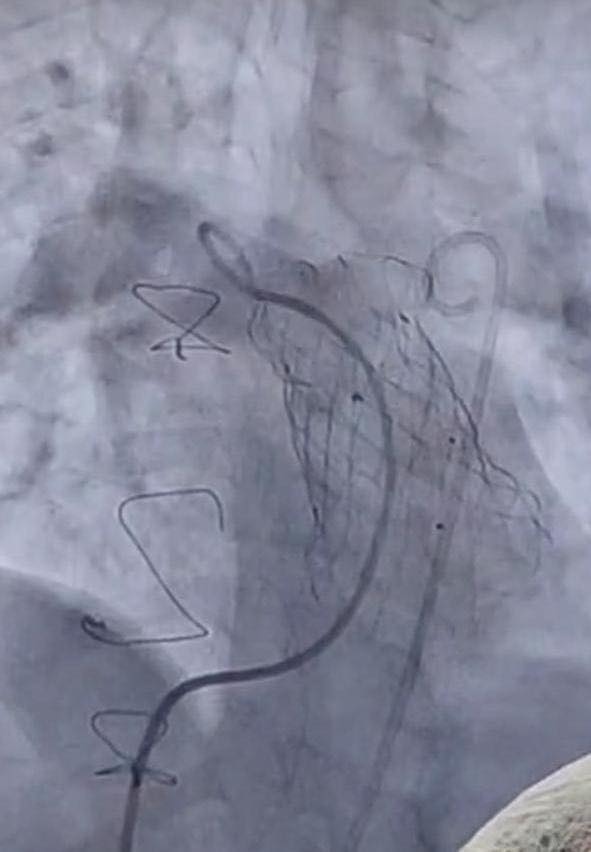

أعلنت وزارة الصحة والسكان، زراعة 12 صمامًا رئويًا، من خلال القسطرة التداخلية العلاجية، داخل معهد القلب القومي التابع لهيئة المستشفيات والمعاهد التعليمية، وذلك خلال 6 أشهر، دون تحميل المرضى أي تكاليف مادية، فيما تبلغ تكلفة العملية الواحدة مليون جنيه، وذلك حرصا من الوزارة على توفير أحدث أساليب العلاج للمريض المصري.

من جانبه، أضاف الدكتور محمد مصطفى عبد الغفار رئيس هيئة المستشفيات والمعاهد التعليمية، أن هذه التقنية تعتمد على القسطرة التداخلية العلاجية في زرع الصمام الرئوي، للمرضى الذين يعانون من عيوب خلقية مركبة بالقلب، وخضعوا لجراحات قلب مفتوح في فترات سابقة، وذلك كبديل عن الجراحة المفتوحة، مشيرا إلى أنه منذ بداية عام 2025 وحتى الآن تم بنجاح زرع 12 صمامًا رئويًا، وغادر المرضى المستشفى خلال 48 ساعة من إجراء القسطرة.